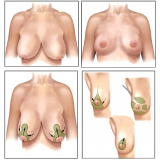

Conheça os procedimentos de excelência para a realização de uma cirurgia plástica a laser!

Quando a prioridade é a saúde, ter por perto boa equipe médica se mostra a melhor opção. Assim, não pense duas vezes: esclareça as suas dúvidas e permita a você ter a assistência de que precisa. Faça uma visita à FF Cirurgia Plástica!